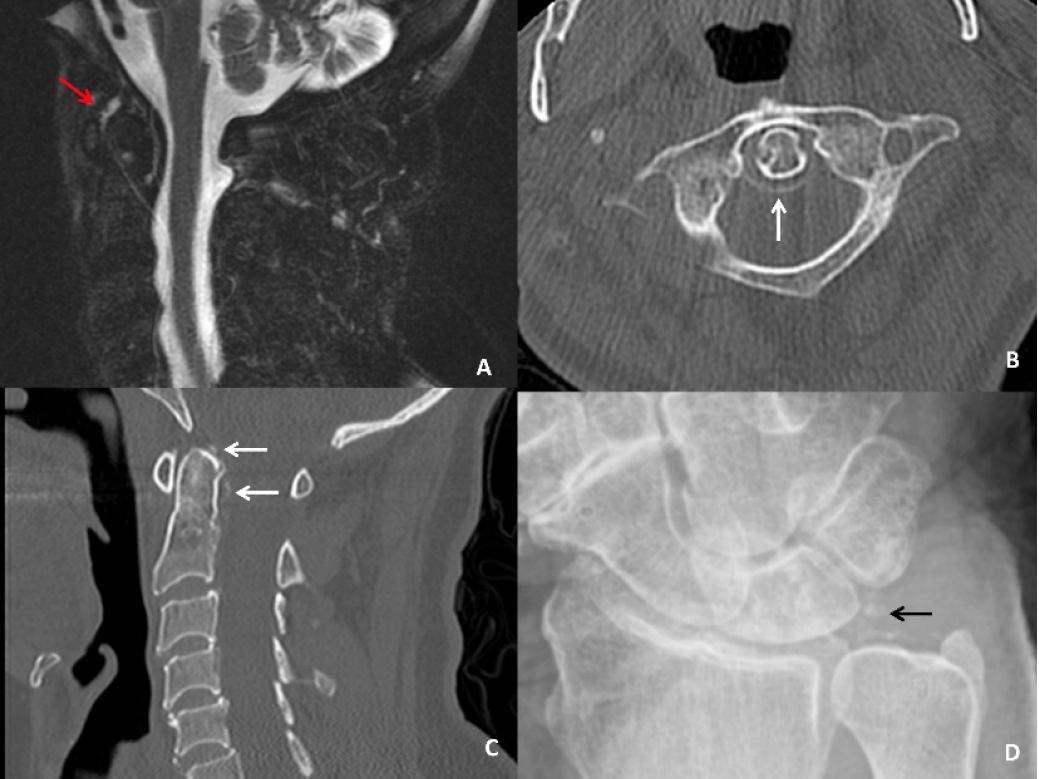

86 years-old Caucasian female presented with sudden-onset, progressively worsening, non-traumatic, severe neck pain, associated with occipital radiation and low-grade fevers. She denied vision changes, jaw claudication, or other joint pain. Past history included one episode of pseudogout involving left wrist. Exam revealed limited range of motion of neck with diffuse cervical tenderness. Bilateral temporal arteries had good pulses and were non-tender. Labs revealed mild leukocytosis, ESR 76 mm/hr, and CRP 137 mg/L. MRI showed multilevel degenerative disk disease without spinal canal stenosis and a small effusion at C1-C2. A review of CT-scan obtained 4 years ago revealed calcification of the transverse ligament of the atlas. Patient was started on oral prednisone 40mg daily, gradually tapered over the next 2 weeks, resulting in complete symptom resolution without any relapse.

Crowned dens syndrome is a rare presentation of calcium crystalinduced neck pain. Typical clinical presentation includes acute-onset, severe neck pain in an elderly patient, often associated with a lowgrade fever and elevated inflammatory markers, correlating with the syndrome’s inflammatory nature [1]. The understood pathophysiology involves deposition of calcium pyrophosphate dehydrate (CPPD) or calcium hydroxyapatite on the soft tissue adjacent to the odontoid process (OP) which can be visualized on computed tomography (CT) of the cervical spine, illustrating localized ‘crown’ or ‘halo’ characteristics of the OP [2,3]. Prognosis is favorable with rapid resolution of symptoms with non-steroidal-anti-inflammatory drugs, or systemic corticosteroids. Clinical presentation can mimic temporal arteritis and meningitis, and radiographic findings can help confirm this diagnosis, preventing further avoidable invasive procedures [4].